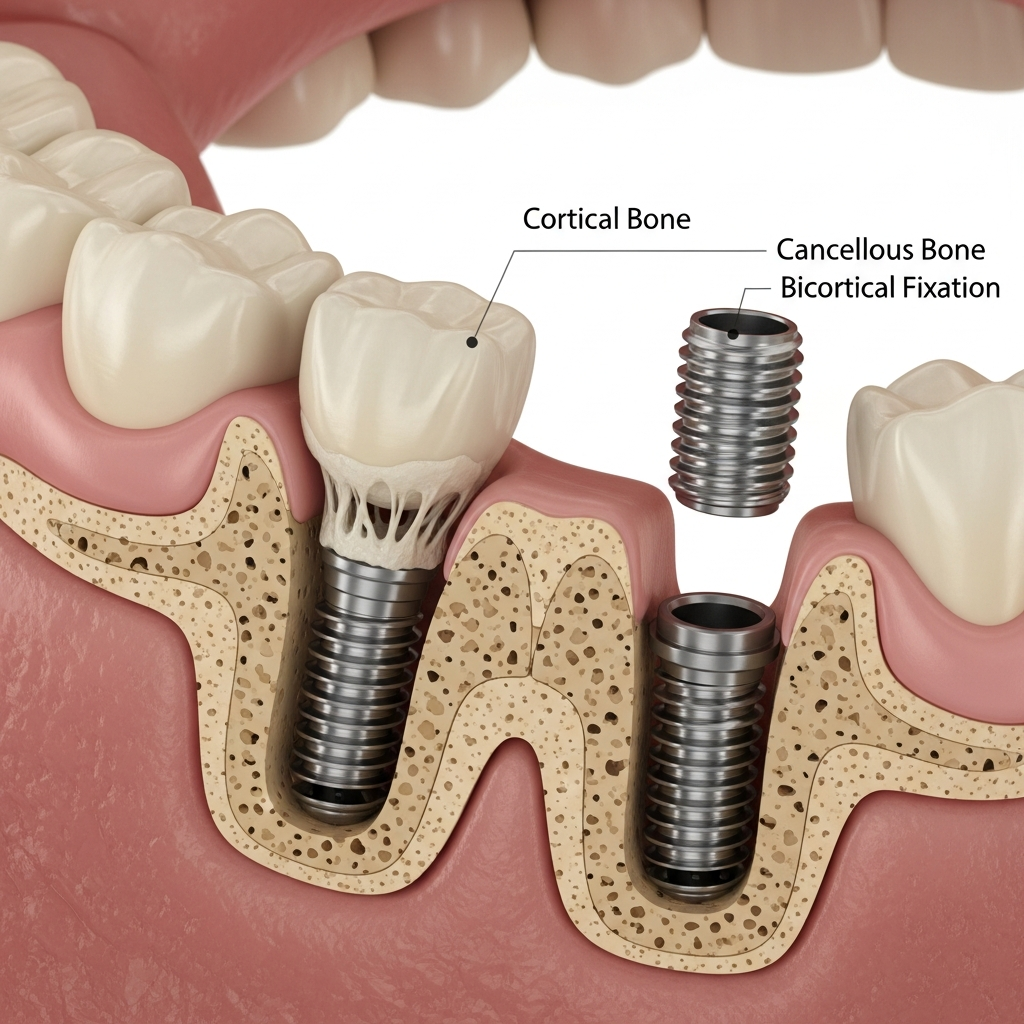

- Design specific: Aceste implanturi sunt adesea monobloc (dintr-o singură piesă), cu o suprafață netedă și filetări laterale, menite să angajeze straturile de os cortical cu densitate mare (osul bazal).

- Ancorare mecanică: Stabilitatea primară nu depinde majoritar de osteointegrarea în osul spongios, ci de blocajul mecanic ferm în două sau mai multe plăci corticale, de unde și denumirea de „bicortical”.

Mecanismul de Stabilitate

Stabilitatea implanturilor bicorticale se bazează pe principiul osteofixării prin inserarea lor în osul cortical rezistent, adesea la nivelul maxilarului superior și inferior. Această fixare robustă minimizează micromișcările și permite transferul forțelor masticatorii direct către structurile osoase dense, contribuind la o predicție bună a succesului pe termen lung, chiar și sub încărcare funcțională precoce.